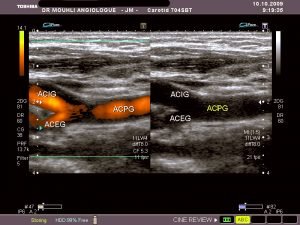

Angiographie numérisée par voie artérielle selective montrant la resténose de la carotide interne à la partie moyenne du bulbe carotidien

Une endoprothèse ou stent est positionnée dans la resténose. La resténose persiste car la force radiale du stent n’est pas suffisante pour écraser la plaque

Un ballon est introduit dans le stent et insufflé (gonflé) pour écraser la plaque fibreuse et rétablir un chenal circulant de bon calibre dans la carotide

Le contrôle angiographique montre le bon résultat de cette angioplastie carotidienne. Le stent dont les mailles métalliques sont visibles permet de maintenir l’artère ouverte